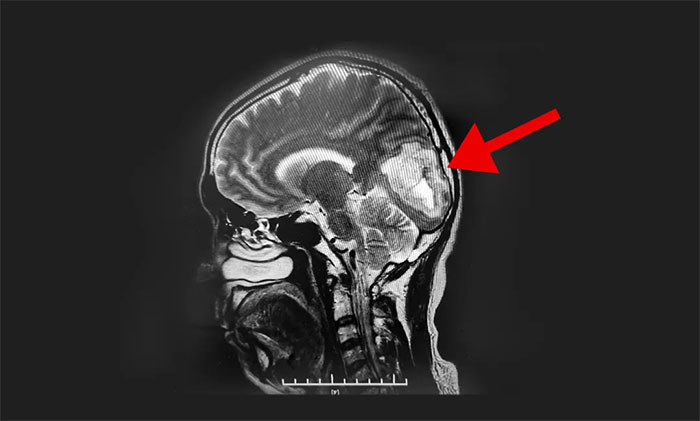

了解到舅舅病情后,曾在上海某三甲醫(yī)院工作的王博士立即通過微信聯(lián)系上海藍(lán)十字腦科醫(yī)院神經(jīng)外科潘仁龍主任。根據(jù)磁共振影像,潘仁龍主任指出:“從片上看,枕葉明確的占位,腫瘤內(nèi)有一個明顯的瘤結(jié)節(jié),伴囊變。雖然腫瘤邊緣環(huán)繞也很明顯,需要檢查胸部,看有無肺部病變,肺部好的就是頭部原發(fā)腫瘤,應(yīng)該在2-3級左右了,具體需要看病理。”一番交流后,王博士建議舅舅到藍(lán)十字腦科尋求進(jìn)一步治療,潘仁龍主任隨即安排好住院相關(guān)事項。

頭顱MRI平掃+增強提示:左側(cè)枕葉占位性病變。根據(jù)患者影像學(xué)檢查,李士其教授、潘仁龍主任、吳治群博士會診認(rèn)為膠質(zhì)瘤可能性大,并造成患者生活質(zhì)量下降,應(yīng)盡快行手術(shù)治療,明確病理診斷。

▲ MR顯示腫瘤超5厘米大小

經(jīng)過充分術(shù)前準(zhǔn)備后,8月23日,李士其教授在吳治群博士、黃秀夫醫(yī)生協(xié)助下為患者進(jìn)行了左側(cè)枕葉腫瘤切除術(shù)。顯微鏡下,李士其教授根據(jù)定位,于左側(cè)枕葉腦組織表面切開,游離腦組織,見深處有暗紅色腫物,考慮為腫瘤,腫瘤質(zhì)軟,呈實性,血供豐富,自四周分離腦組織與腫瘤,并切除腫瘤,向右切除至大腦鐮,向下、向深處切除至小腦幕,向上、向左側(cè)切除至腫瘤邊界外,在充分保護神經(jīng)功能的前提下,歷時約五小時,最終5公分大的腫瘤被順利切除。